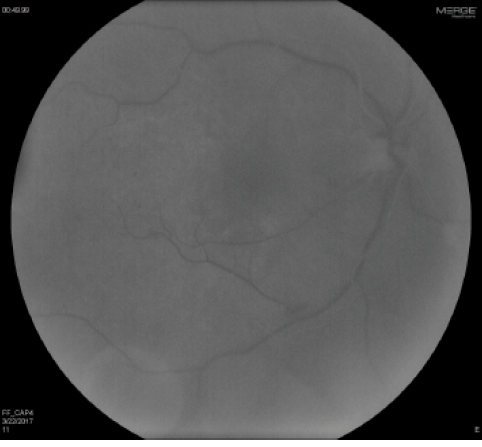

Figure 2. Fundus photograph OD demonstrates retinal whitening in the nasal macula and parafoveal area with drusen and intraretinal hemorrhages.

Anterior segment examination OD revealed a deep and quiet anterior chamber with a 2+ nuclear sclerotic cataract. Fundoscopic examination was notable for a lack of vitreous inflammation, an optic disc with sharp margins, a cup-to-disc ratio of 0.7, and parafoveal retinal whitening with the presence of a cherry red spot (Figure 2). Scattered intraretinal hemorrhages were seen in the posterior pole and periphery, along with mildly dilated and tortuous retinal veins.

Figure 3. FA OD reveals lack of retinal filling at 49 seconds, indicating a perfusion delay.